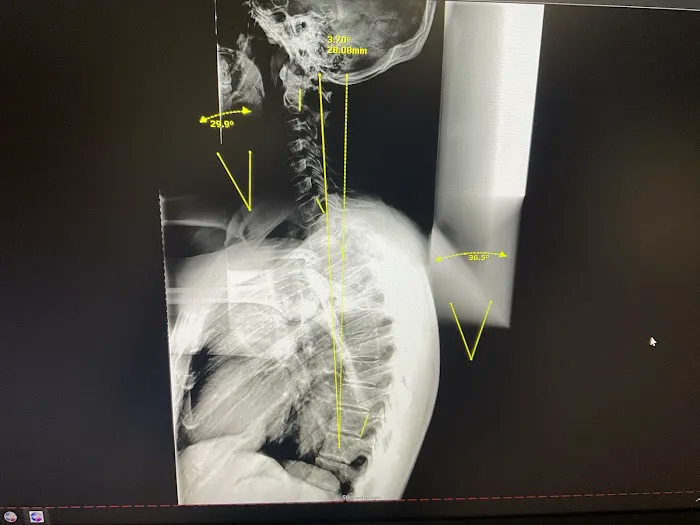

- Posture Correction: Addressing postural imbalances that can contribute to pain and discomfort, helping patients improve their alignment and reduce stress on their spine and joints.